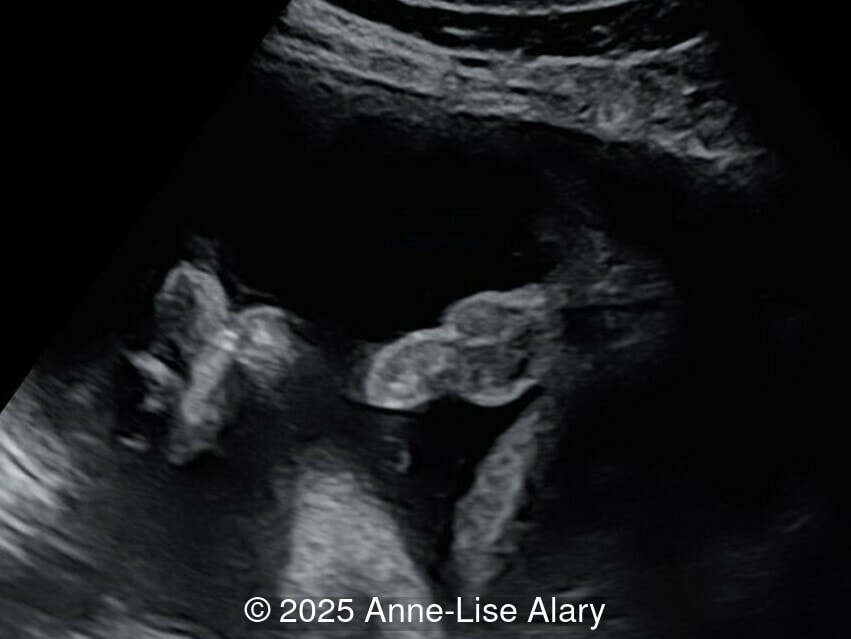

Axial image of the perineum

Image 4 Axial image of the perineum

Our prenatal ultrasound revealed a male fetus with megabladder, dilation of both ureter and kidneys, and thinned kidney parenchyma consistent with Lower Urinary Tract Obstruction (LUTO).  Additional findings suspected on ultrasound and confirmed on computed tomography included:

• Dysostosis: Hemivertebrae L3, fused L4-L5, abnormal left foot with short metatarsals and missing phalanges

The diagnosis of PBS is often made in the second trimester of pregnancy, although it has been described as early as 11 weeks of gestation [20]. The most frequent ultrasound findings are a large, thin-walled bladder accompanied by bilateral hydroureter/hydronephrosis, dysplastic kidneys with echogenic renal parenchyma and renal cortical cysts, and abdominal wall laxity which is better viewed after bladder decompression [21]. Cryptorchidism can be detected prenatally by 28 to 30 weeks gestation when the testes descend into scrotum. There may be a patent urachus, visible as a cystic connection between bladder and umbilicus. Oligohydramnios is a frequent finding, which makes it difficult to visualize the associated anomalies.